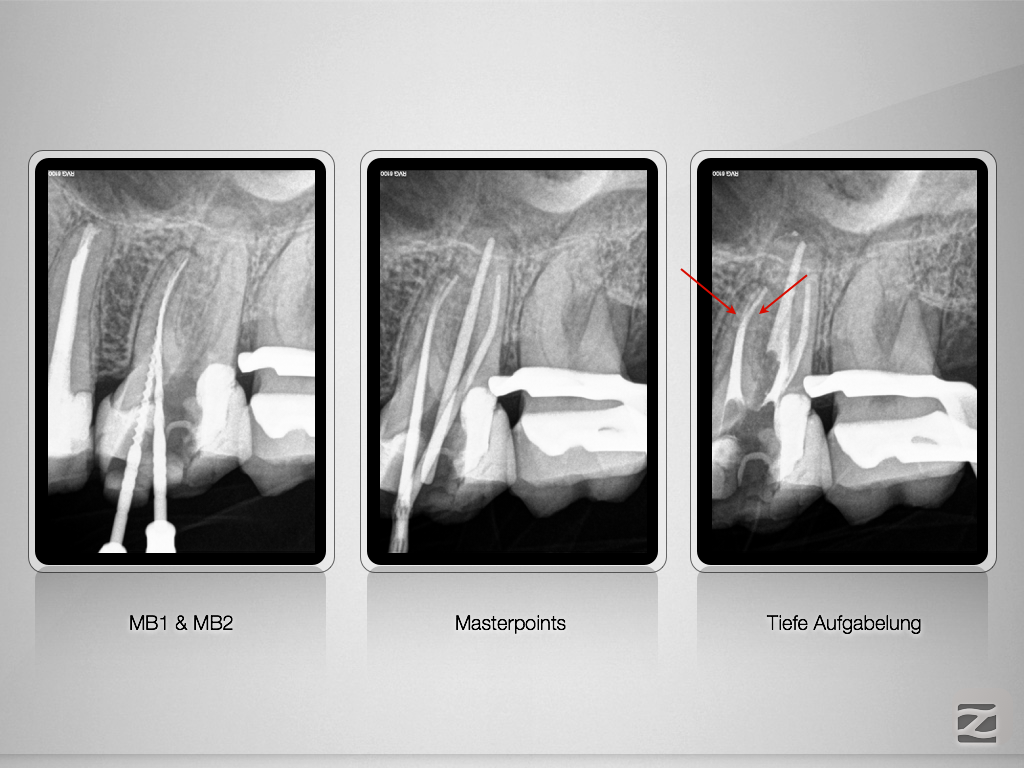

Navigierte Aufbereitung